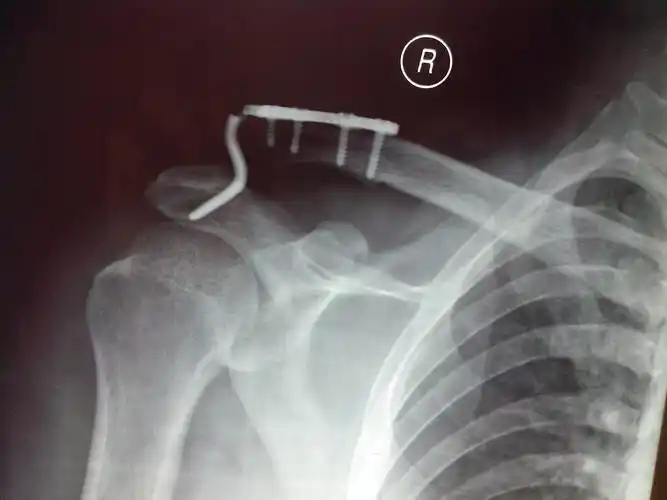

刚做的一例锁骨骨折 [病例帖]

创伤 辅助检查:x线(2017-08):右侧锁骨骨折术后钢板断裂,骨折复位丢失

肩锁关节脱位锁骨远端骨折关节镜下微型钢板固定喙锁 斜方韧带重建术

锁骨钩钢板的固定术后5月钩断裂